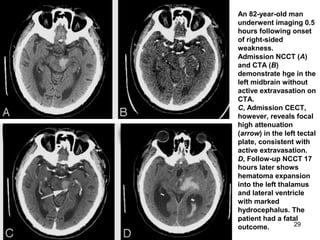

An 82-year-old man

underwent imaging 0.5

hours following onset

of right-sided

weakness.

Admission NCCT (A)

and CTA (B)

demonstrate hge in the

left midbrain without

active extravasation on

CTA.

C, Admission CECT,

however, reveals focal

high attenuation

(arrow) in the left tectal

plate, consistent with

active extravasation.

D, Follow-up NCCT 17

hours later shows

hematoma expansion

into the left thalamus

and lateral ventricle

with marked

hydrocephalus. The

patient had a fatal

outcome.